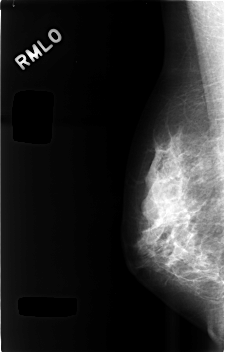

C_0494_1.RIGHT_MLO

RIGHT_CC LINES 4600 PIXELS_PER_LINE 2928 BITS_PER_PIXEL 12 RESOLUTION 50 NON_OVERLAY

RIGHT_MLO LINES 4568 PIXELS_PER_LINE 2920 BITS_PER_PIXEL 12 RESOLUTION 50 NON_OVERLAY